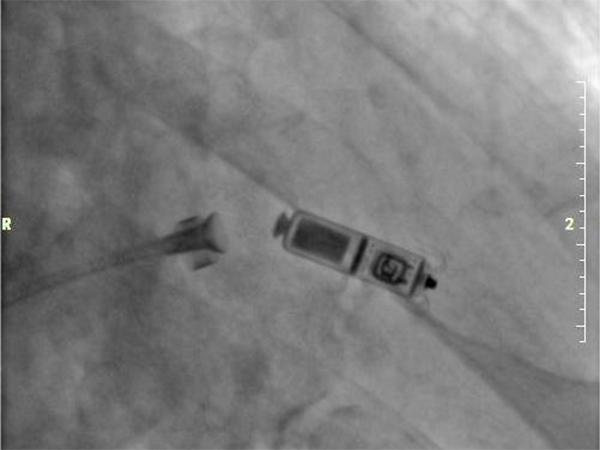

手術(shù)在科主任梁田帶領(lǐng)下,電生理團(tuán)隊(duì)劉敏主任、盧磊主任共同上臺(tái)完成。在局部麻醉下,通過(guò)股靜脈穿刺,將起搏器通過(guò)導(dǎo)管植入到心腔內(nèi)部,術(shù)中Micra AV無(wú)導(dǎo)線起搏器僅一次釋放即成功,釋放位置精準(zhǔn),手術(shù)全程時(shí)間約40分鐘,患者術(shù)后反應(yīng)良好,6小時(shí)后即可下床走動(dòng)。

1. 體重更輕、體積更小。大小似一粒維生素膠囊,體積約1.0cm3(相較于傳統(tǒng)起搏器減小了93%),長(zhǎng)度為2.59cm,重量?jī)H有1.75g。